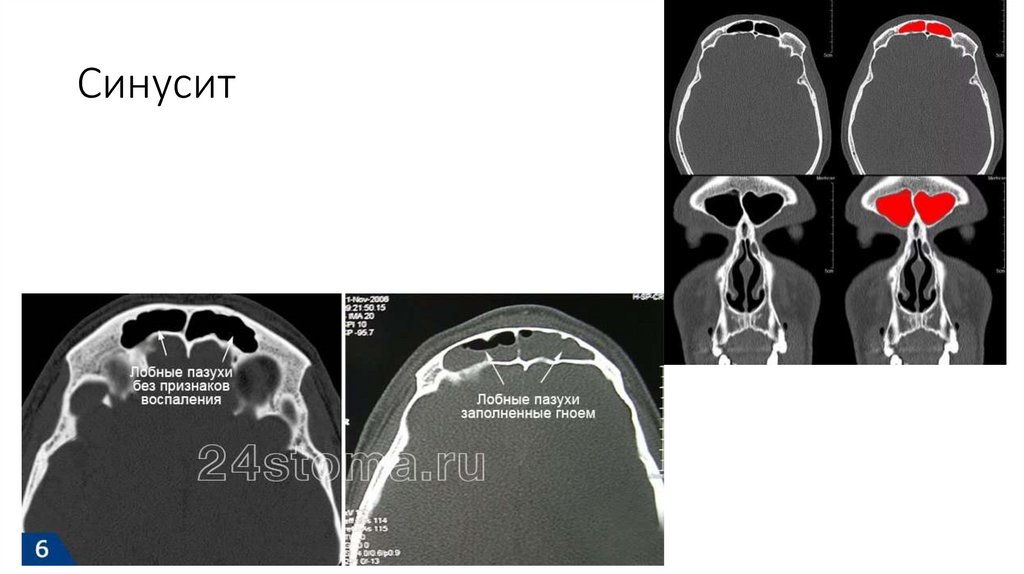

Синусит